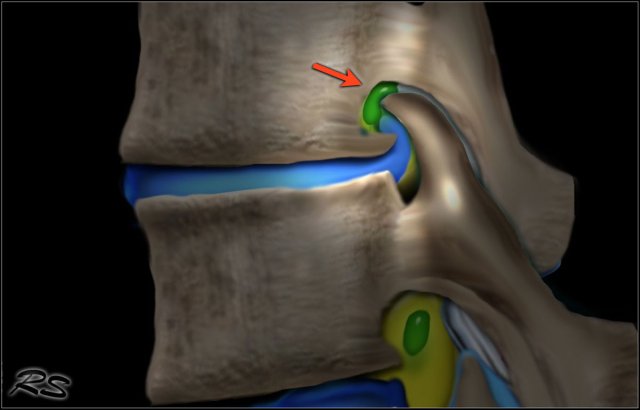

The illustration demonstrates the structures that surround the nerves within the spinal canal.

Flavum ligament

The flavum ligament is a strong ligament on the interior posterior side of the vertebral canal that connects the laminae of adjacent vertebrae.

As a result of aging and instability of the vertebral column due to facet arthrosis there will be more stress on the flavum ligament resulting in hypertrophy and fibrosis.

Hypertrophy of the flavum ligament is usually seen in combination with facet arthrosis and both result in stenosis of the lateral recess or when it is bilateral, in spinal stenosis.